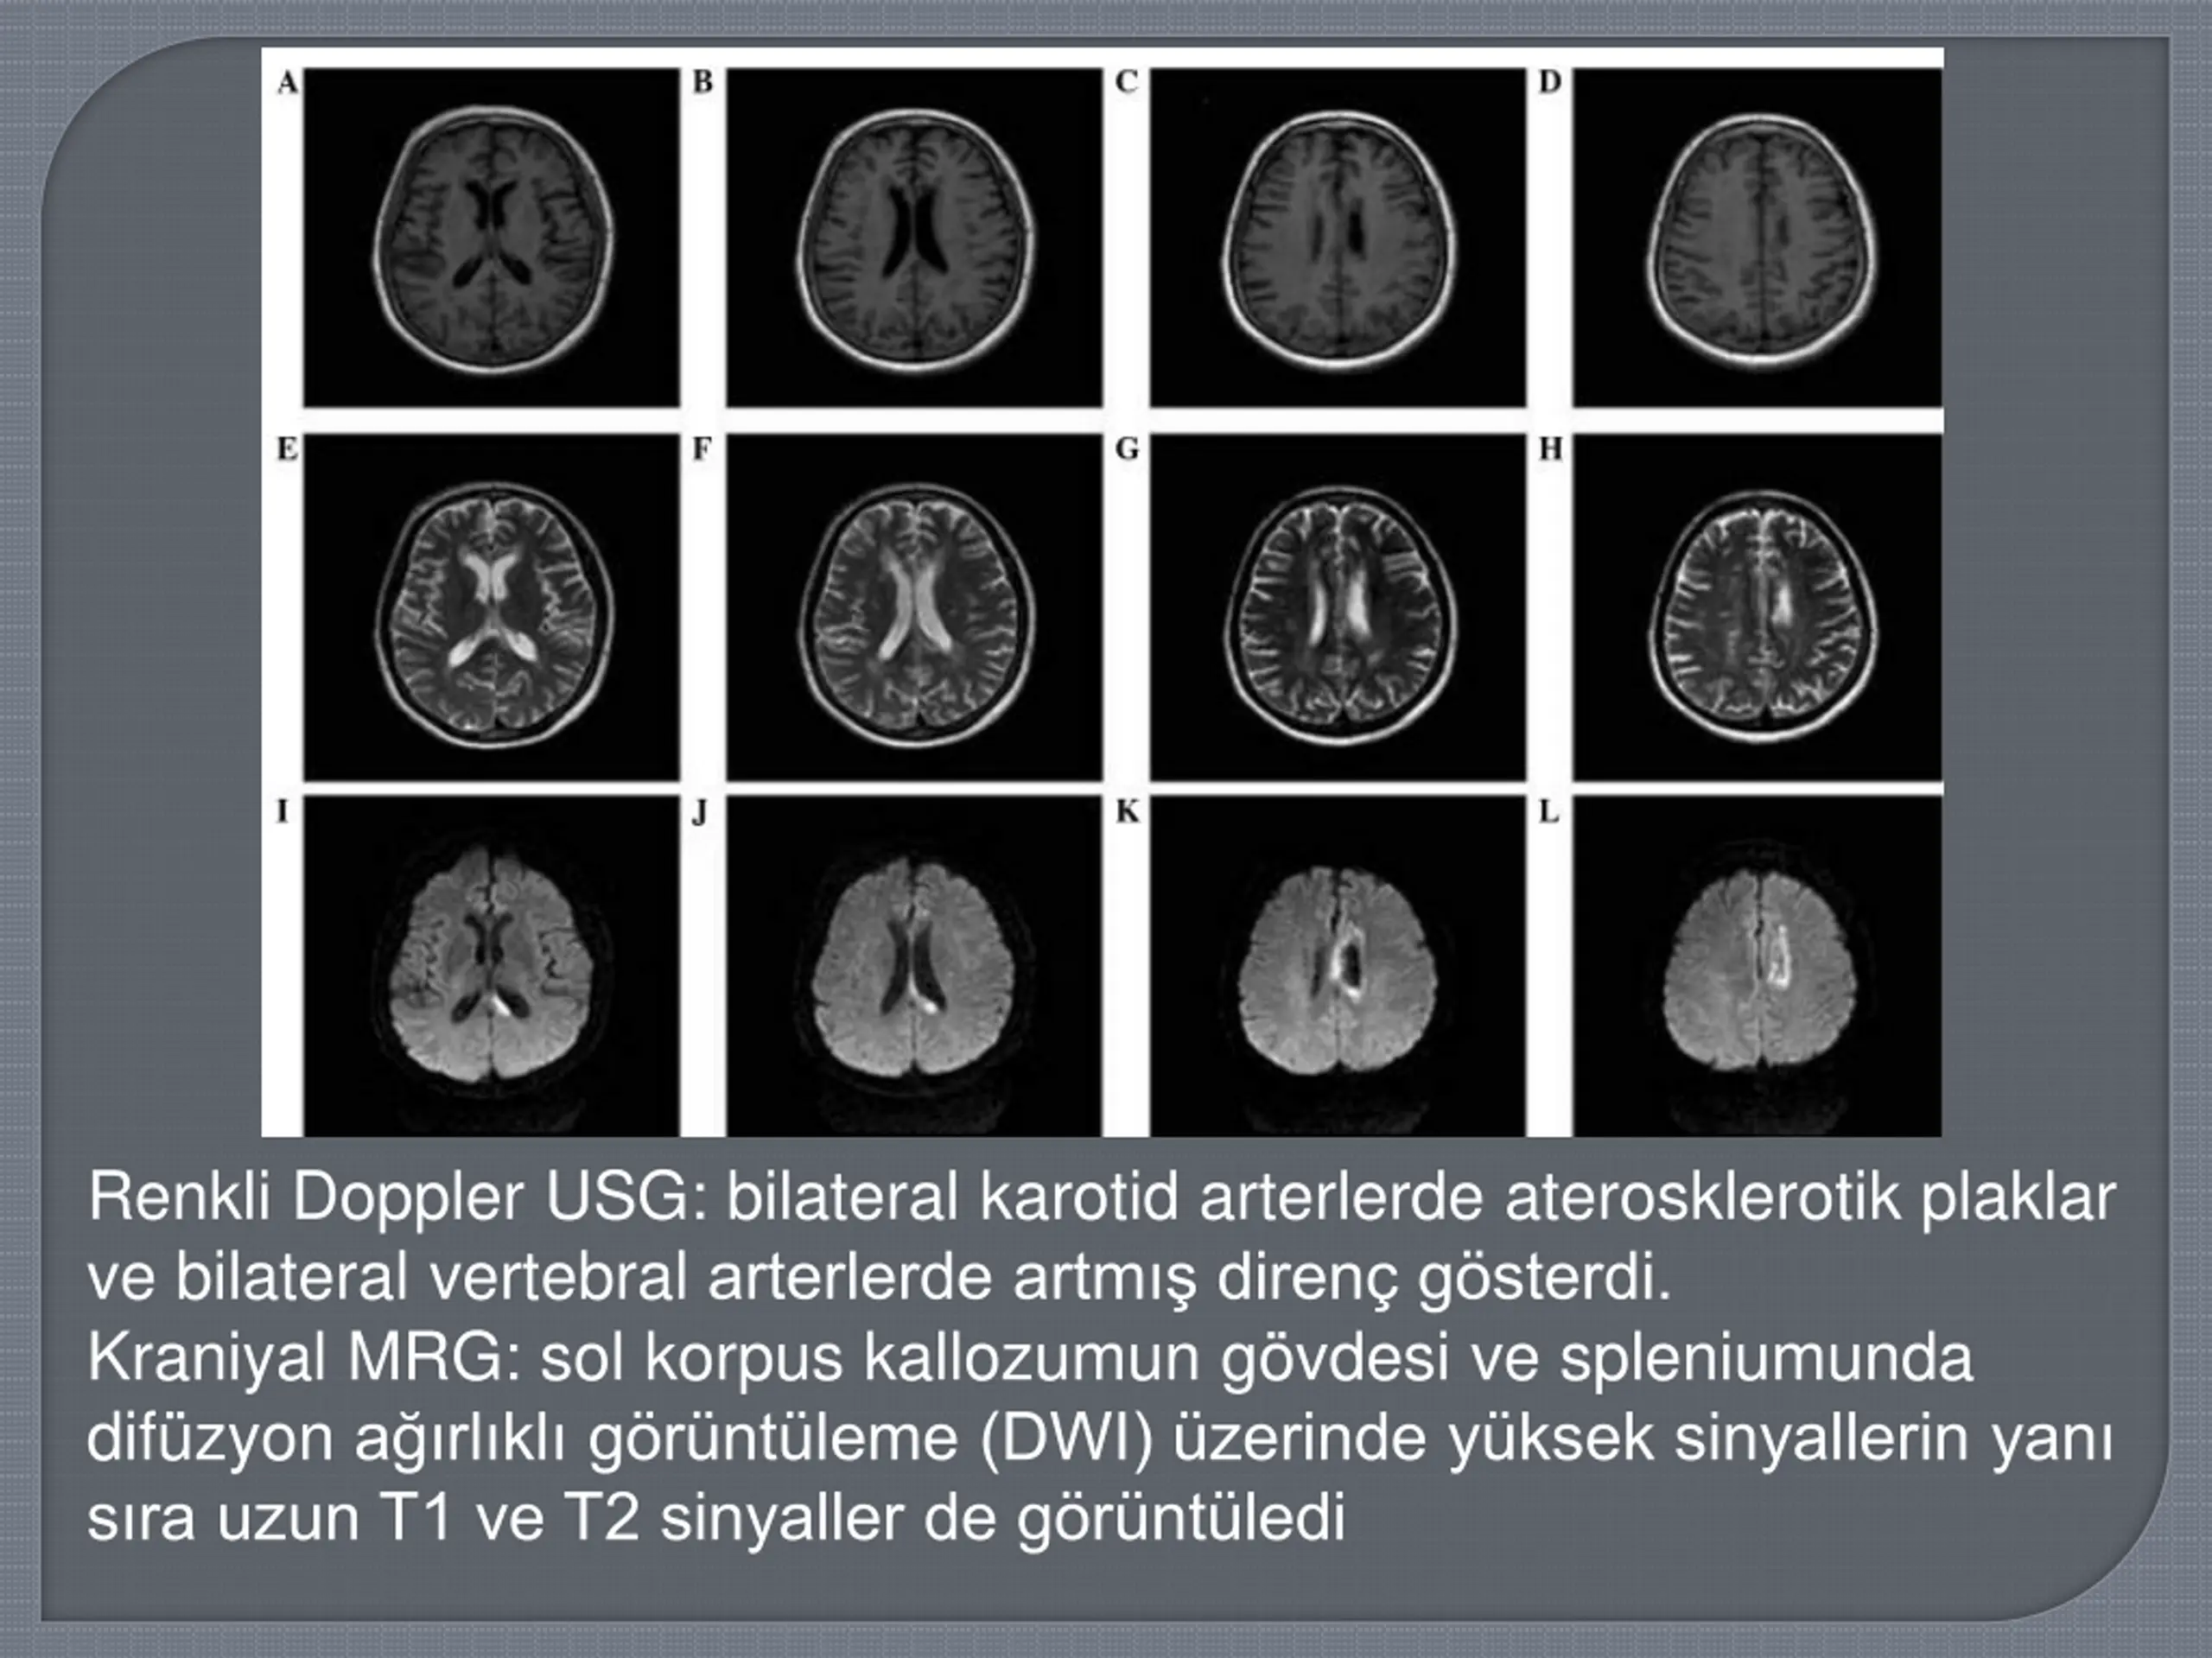

Renkli Doppler USG: bilateral karotid arterlerde aterosklerotik plaklar ve bilateral vertebral arterlerde artm diren g sterdi. Kraniyal MRG: sol korpus kallozumun g vdesi ve spleniumunda dif zyon a rl kl g r nt leme (DWI) zerinde y ksek sinyallerin yan s ra uzun T1 ve T2 sinyaller de g r nt ledi